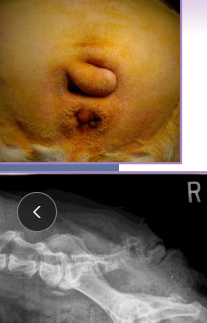

Episioplasty: Vulvar folds

overweight dogs, younger recessed vulva

En-bloc resection: Tail folds

Bulldogs

Redundant skin overlaps a deformed terminal

caudal vertebrae & prone to 2ndary infections